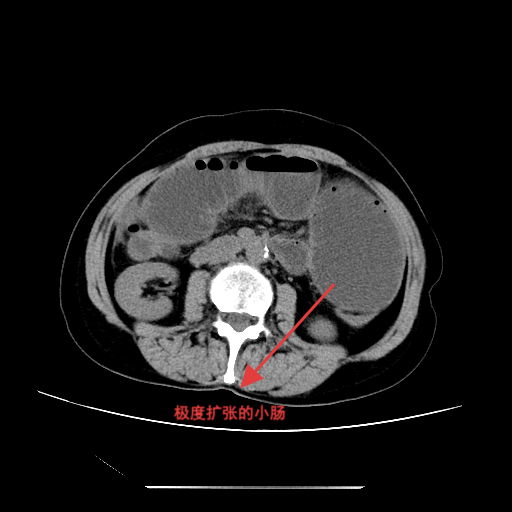

▲腹部CT所见

入院后,完善相关检查,腹部立位平片提示肠管扩张,可见多个液气平面,结合病史考虑术后肠梗阻。经综合评估,决定先行保守治疗,在胃肠外科和疝外科刘奇副主任医师团队协作下,为患者置入肠梗阻导管。置管后,患者腹胀、腹痛症状明显缓解,胃肠减压引流通畅,肠鸣音逐渐恢复。经精心护理及营养支持,患者肛门排气排便恢复正常,复查腹部平片示肠管扩张较前明显改善,无液气平面。病情持续好转,顺利出院。